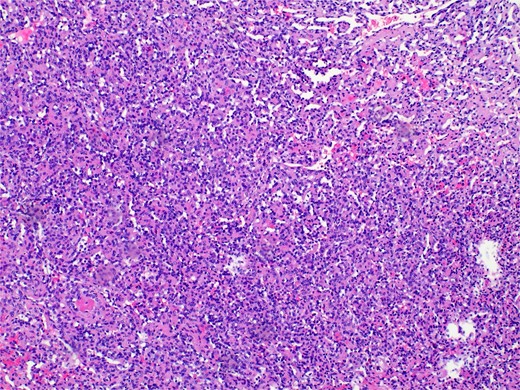

Pathology revealed a benign vascular neoplasm, whose morphological pattern favored AH (Figs 3 and 4).

Histopathology micro findings showing scattered “hobnail” cells.